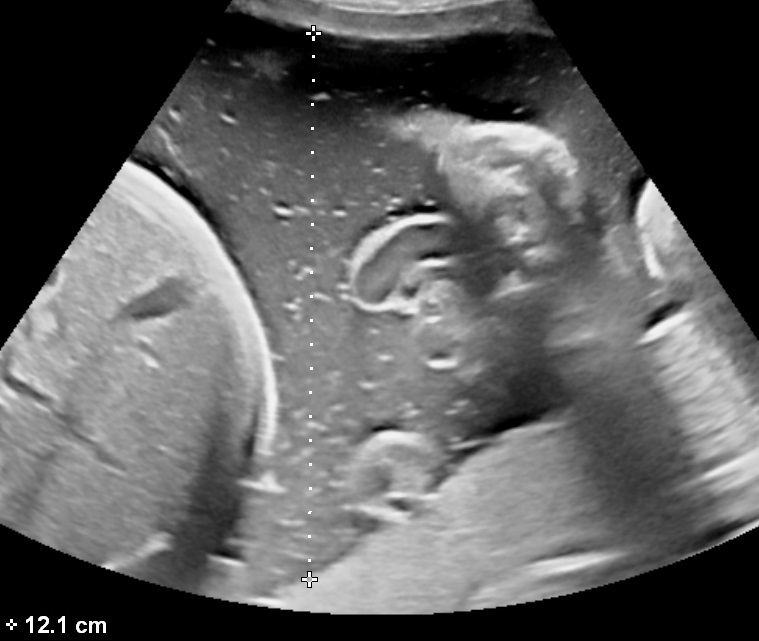

- Single Deepest Pocket (SDP)

The measurement is performed with the ultrasound probe at a right angle with the uterine wall. Measurements should exclude the umbilical cord or fetal parts. The width of each measured pocket must be at least 1 cm. Normal values range between 2-8 cm. It is also the preferred method for estimating the amniotic fluid volume in twin pregnancies.